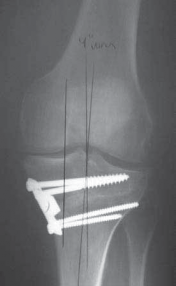

A C B D TECH FIG 7•A.

B.

Intraoperative final AP radiograph.

C,D.

Postoperative AP and lateral radiographs.